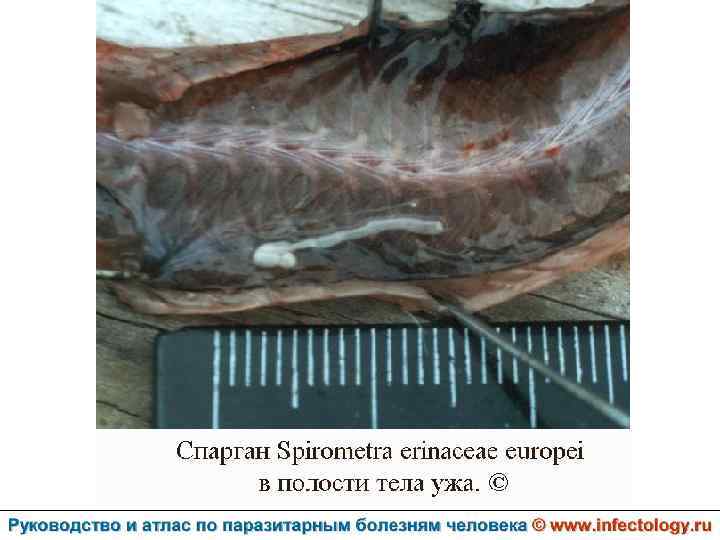

Спарганоз (шифр по МКБ 10 – B 70. 1) – зоонозный биогельминтоз, возбудителем которого служит личиночная стадия - плероцеркоиды (Sparganum) - цестоды Spirometra erinacei europaei. Характеризуется главным образом поражением глаз, а также подкожной клетчатки и внутренних органов.